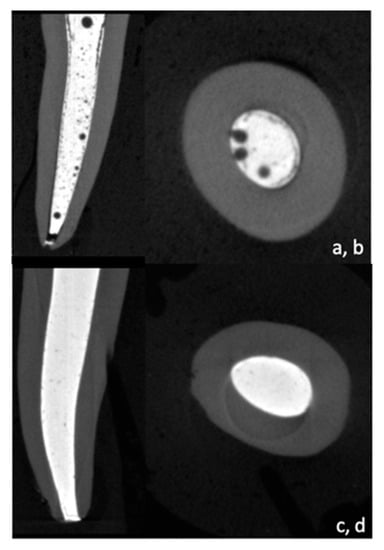

2.4. Micro CT Scanning

- Complete root with filling

- Complete filling with voids

- Filling without voids

- C: Canal (filling + voids)

- F: Filling without voids

- V: Voids

- Cc, Fc, and Vc for the coronal part

- Cm, Fm, and Vm for the middle part

- Ca, Fa, and Va for the apical part

3.1. Micro-CT